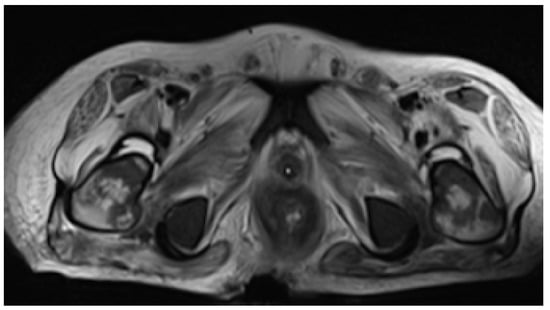

Despite being on ARV therapy since day +46 as previously mentioned, during an approximate three-week interval, HIV viral load increased from 36,904 (day +9) to 795,000 copies/mL (day +68). Additionally, on D6 of oral tecovirimat therapy, there was progression of skin ulcerations and extensive destruction of the perineum and gluteal region, with evidence of fistulization to rectum and prostate on abdominopelvic CT. For this reason, a protective colostomy was performed on day +73 to prevent contamination of the perineal lesions and allow for cicatrization to occur. In addition, CT scan showed jejunal and colic increased mucosal contrast uptake, suggesting enterocolitis (Figure 3). These facts raised concerns about probable insufficient enteric absorption of ART and tecovirimat considering the progressive gastric content stasis and enterocolitis documented on CT and therefore possible extension of inflammatory process to small bowel. This situation prompted the search of a parenteral option to both medications. On day +73 intravenous (IV), cidofovir (5 mg/kg once weekly for 2 weeks, then once every other week, following WHO interim guidance June 2022) was added to oral tecovirimat (which completed 21 days) as antiviral therapy for mpox. HIV viral load increased to 5,000,000 copies/mL, and TCD4+ dropped to 38/μL on day +75, and there was confirmation of no other mutation than M184V in contemporary resistance testing along with no mutations detected for the integrase gene. Together with viral enteropathy—the tissue had abundant inflammatory cell infiltrate and villous atrophy—reported in duodenal biopsy on day +86, which was also PCR-positive for mpox, confirmed the likely lack of absorption of oral BIC/TAF/FTC. A full parenteral regimen with intramuscular (IM) cabotegravir (CAB) and IM rilpivirine (RPV) was started on day +95, both to be administered monthly, with initial dosing of 600 mg of CAB and 900 mg of RPV together with IV zidovudine 50 mg every four hours. Six days after the initiation of the later regimen, there was already a decrease in HIV viral load from 5,000,000 to 9010 copies/mL (Table 1).

Figure 5. Pelvic MRI demonstrating deep gluteal-sacral soft tissues lesion causing severe barrier loss of integrity with rectal exposure.